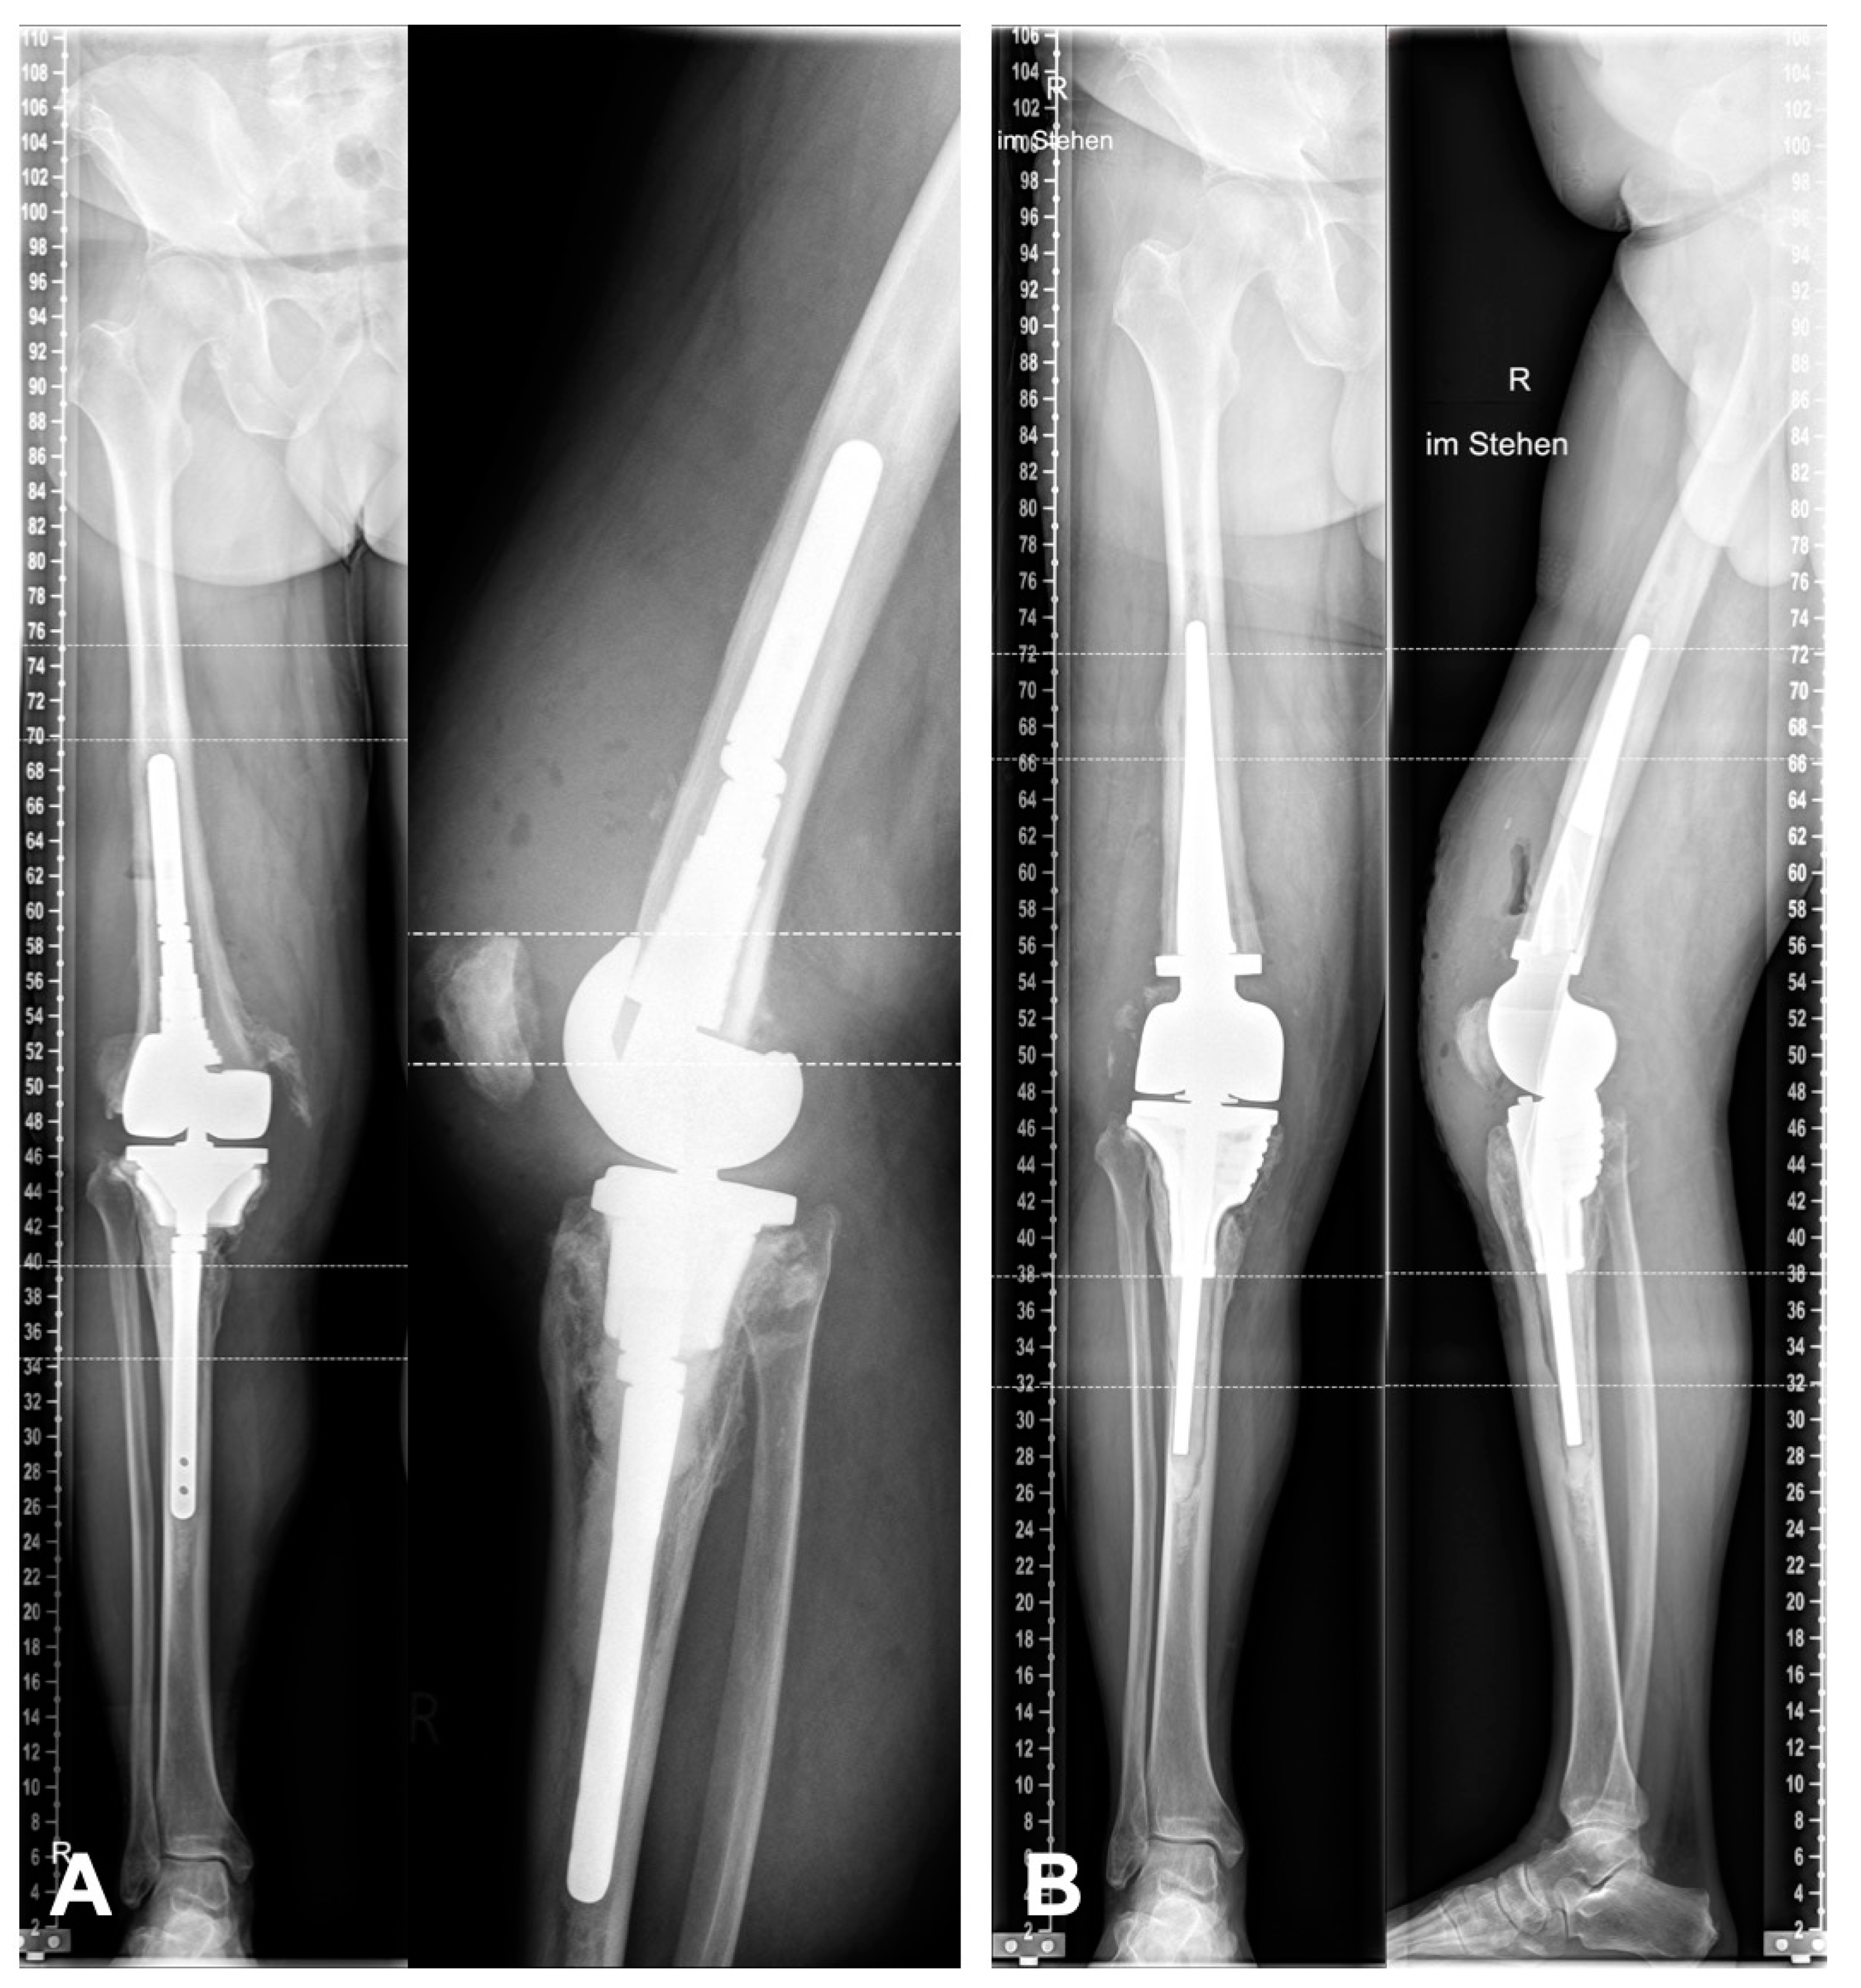

Ten patients who were treated with individual custom-made 3D-printed knee revision implants were included. The basis of the knee system was the Link® Endo-Modell rotating-hinge system (RTH) and Megasystem-C distal femoral replacement (DFR) (Waldemar Link GmbH & Co. KG, Hamburg, Germany). All patients were treated between March 2019 and May 2020. The minimum follow-up was 12 months. The mean patient age at the time of surgery was 68.4 years (range 59–79). Inclusion criteria were a two-stage revision due to late-onset or chronic PJI as well as severe bone defect after aseptic loosening. All bone defects were AORI type III and could not be treated with a standard cone or stem (Figure 1A). All patients were treated with an antibiotic static cement spacer in the two-stage revision interval. No aspirations were routinely performed before the second-stage revision. There were no exclusion criteria. All surgeries were performed by a single senior surgeon. Approval for this retrospective case series was given by the institution’s review board (8439_BO_K_2019). Informed consent was obtained from all subjects involved in the study.

Figure 1.

(A) Preoperative X-rays before explantation of the septic prosthesis. (B) Postoperative X-rays after reimplantation. The joint line and limb alignment are fully reconstructed. (R = right).